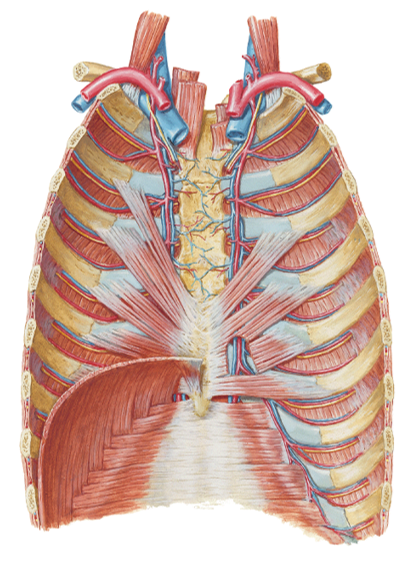

show what the superior thoracic aperture and inferior thoracic aperture are?

notice how in the first picture the esophagus and trachea, nerves and BV's are popping through

what does the superior thoracic aperture contain?

what does the inferior thoracic aperture allow?

- Superior...contains esophagus, trachea, nerves & blood vessels that supply the head, neck and UE

- Inferior...allows the esophagus, IVC (inferior vena cava) and aorta to pass inferior to abdominal cavity

describe what the external intercostal muscles do during inhalation? what do the ribs do? what does the sternum do?

what does the diaphragm do?

the external muscles contract causing the expansion of the chest cavity and an influx of air into the lungs

ribs elevate

sternum flares

diaphragm moves inferiorly during contraction

notice the external intercostal muscles

look at picture

what muscle do you see here and how do you know?

innermost intercostals because you can see the nerve and vessels driving into the muscle indicating that you can see the innermost intercostals (you are looking inside the chest so the IM are the deepest muscles inside)

Transversus thoracis (TT) (in front)...expiration (depress

ribs)...located on internal anterior thoracic cage...in 1st

picure

Subcostal (SC) muscles (in back and on

inside)...inspiration (elevate ribs)...located on internal posterior

thoracic cage (in second picture they are the strips going up)

notice the R and L phrenic nerve going down to attach to the diaphragm

in picture: all regions form around the central tendon...small spot above is the sternal part...two huge kidney shapes on sides of central tendon are the costal regions...and the lumbar region is the space underneath the central tendon

in picture you are looking from the top down...the CDR is wrapped around the 2 mickey mouse ears on the side where the ribs and diaphragm meet...the CMR is the small corners below the front circle on either side (slightly more yellow in color)

notice how the lung doesnt go all the way down and how there is a small corner where there can be an accumulation of fluid in the CDR

notice the cardiac notch in the CMR and how that can leave more space for the heart

the CDR is on the bottom of the lung in the kiddie-corner

the CMR is seen when you look down on the diaphragm from the top and see a small space in front